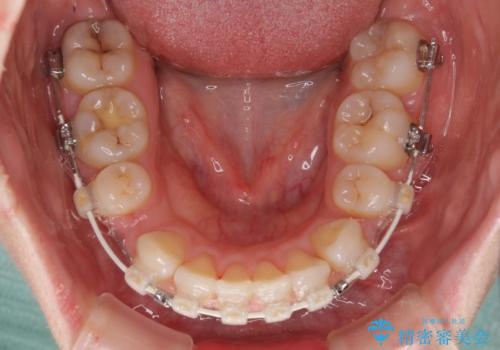

- 矯正装置

- 審美装置

- 2年6ヶ月

元々上下正中の位置はずれていましたが、治療中によりズレが大きくなったので、元の位置に戻すため治療期間を余計に要しました。